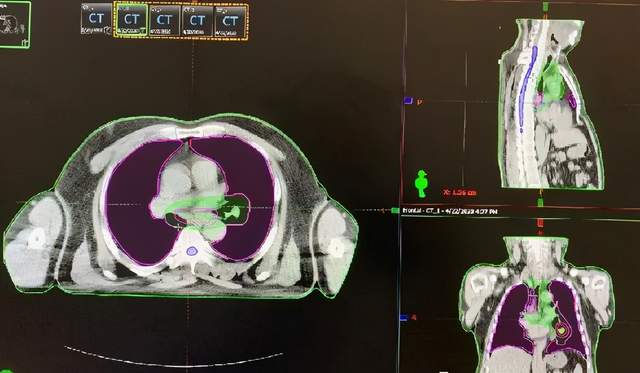

乳腺癌术后辅助放疗

保乳术后放疗

小细胞肺癌放疗